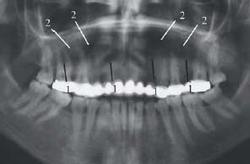

Some anatomic structures can look disturbing on panoramic images. The prominent radiolucency at the apices of the mandibular incisors (above) is simply the mental fossa (3).